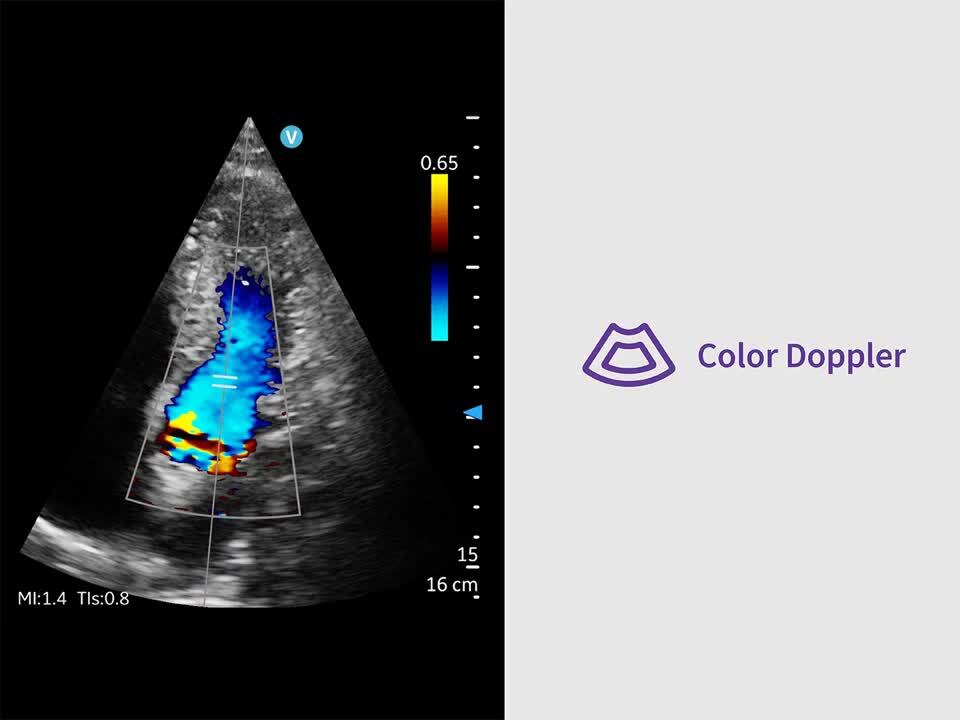

Image quality you can be confident in

Key features for all users and specialties